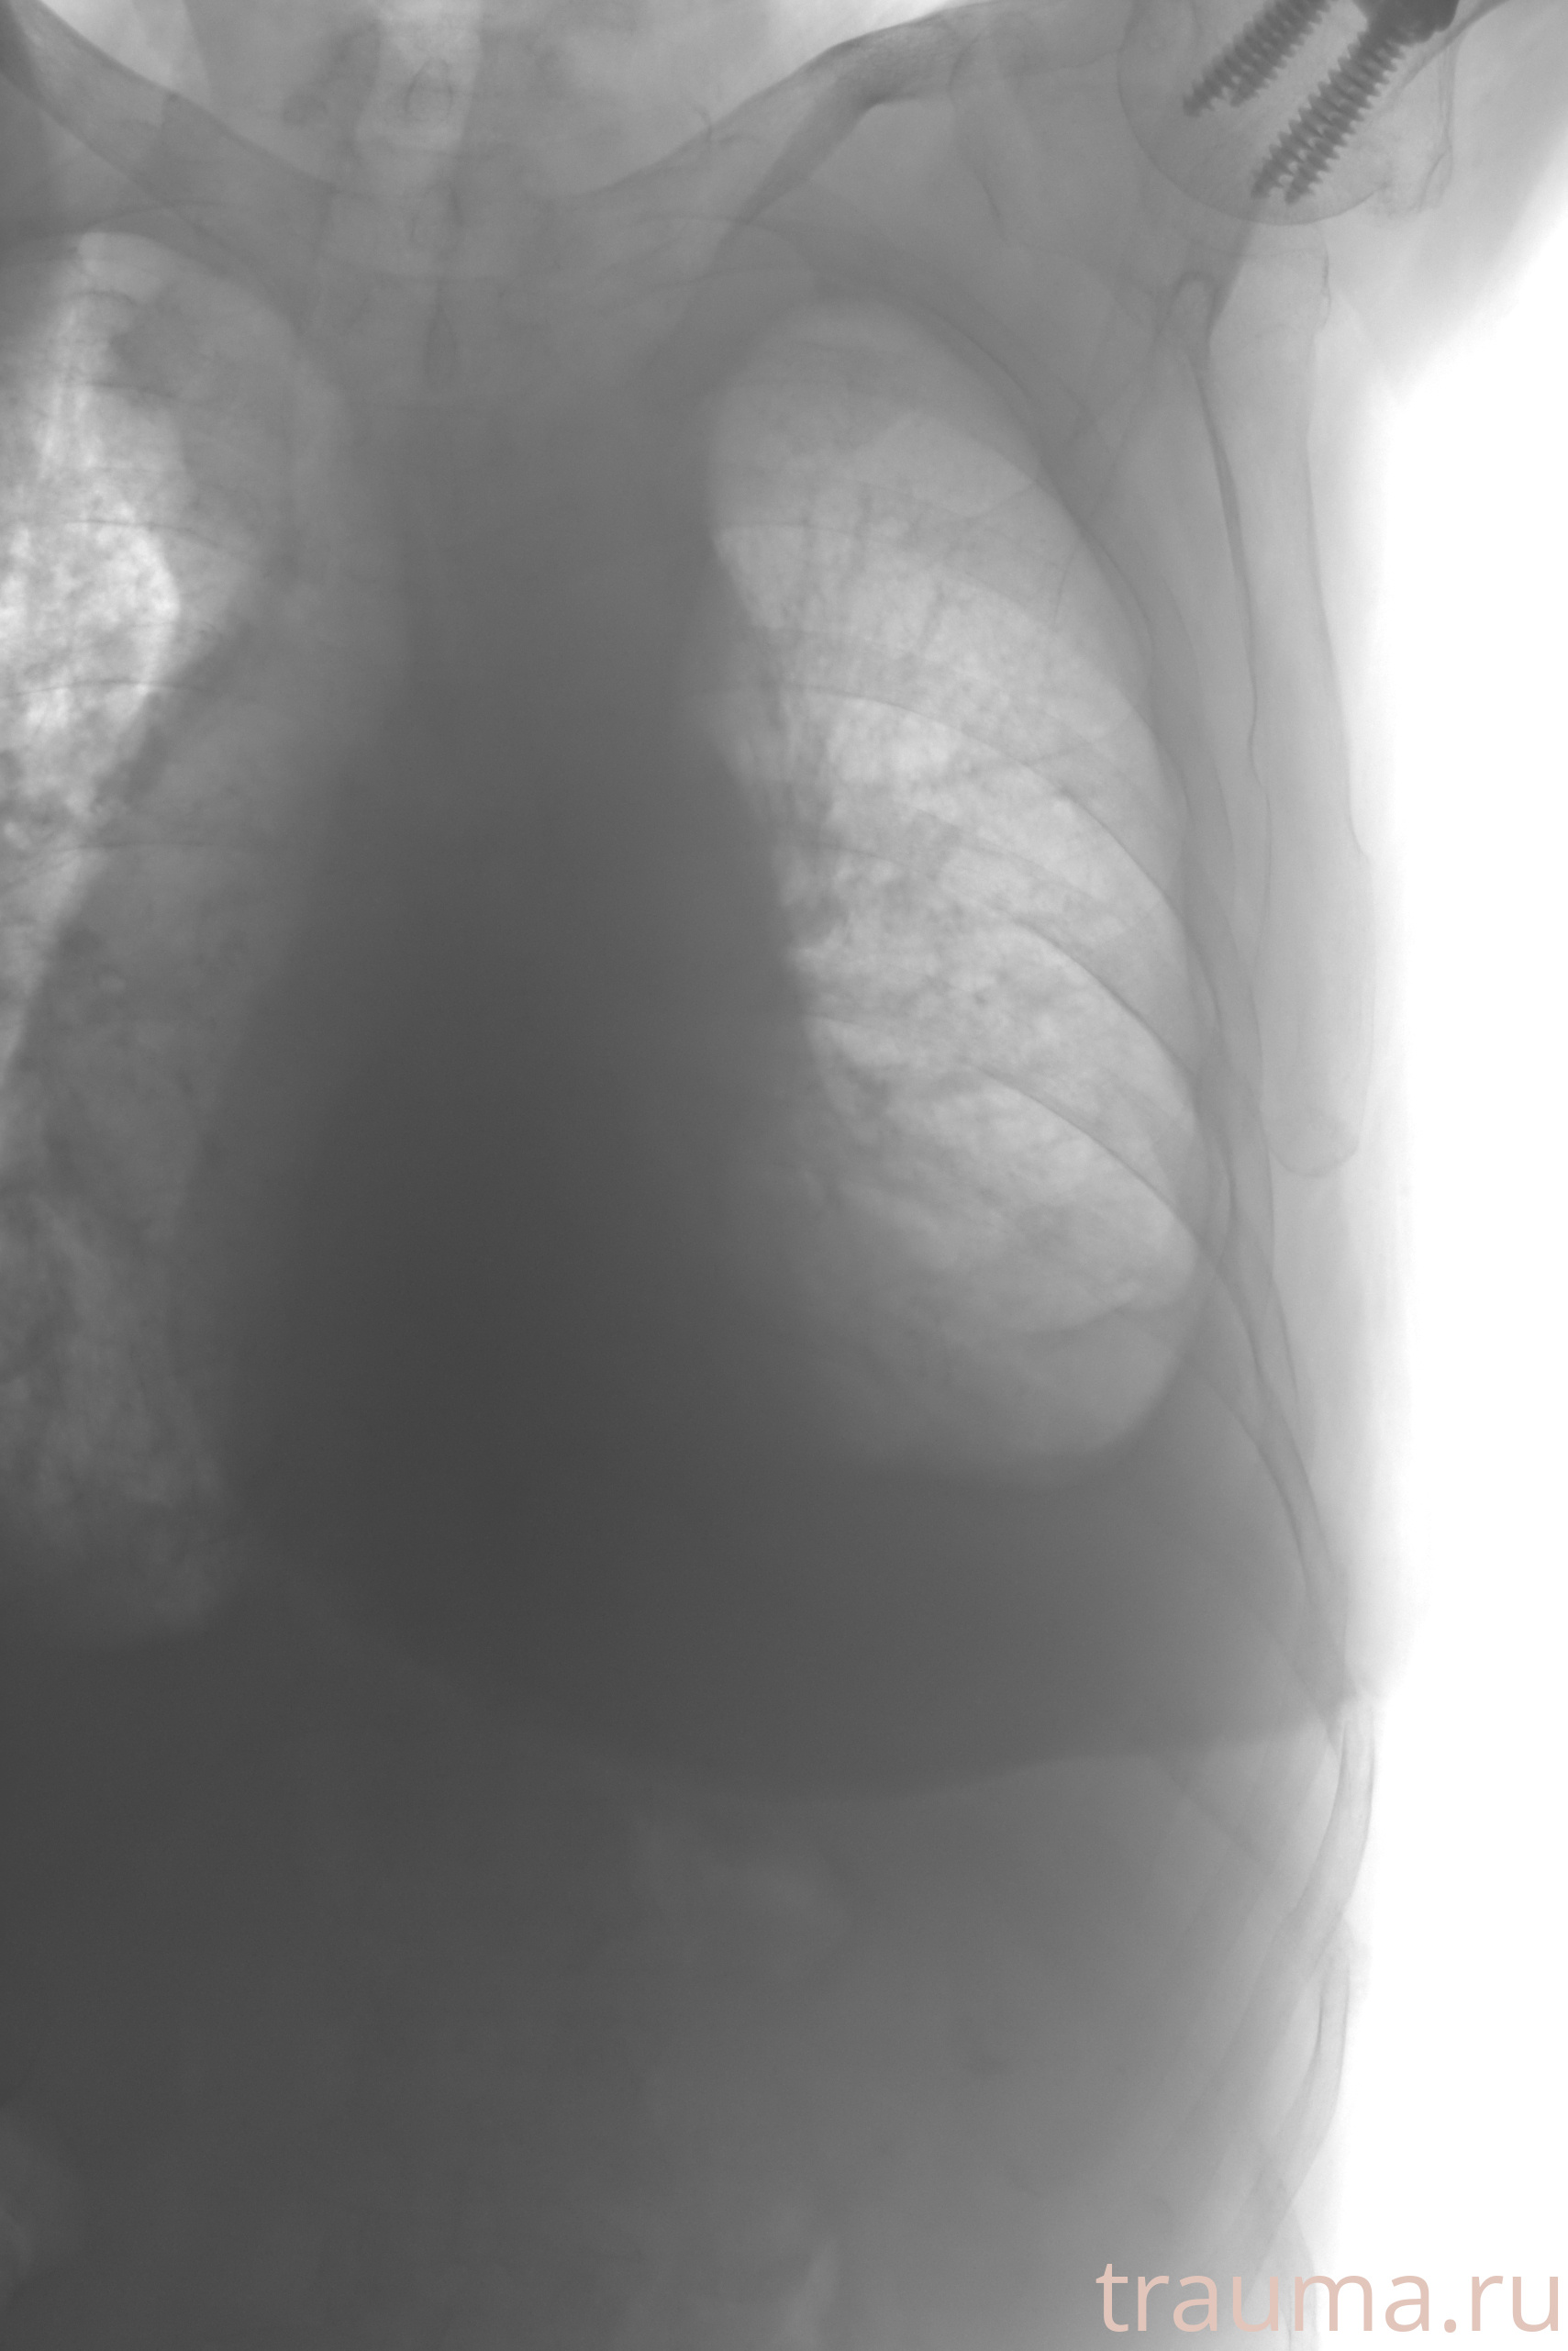

Рентгенограммы

Рентген на дому: по вашему адресу приезжает врач-рентгенолог, травматолог-ортопед с мобильным рентгеновским аппаратом, проводит диагностику травмы или заболевания, делает необходимые рентгенограммы, дает рекомендации по дальнейшему лечению. Получить качественные снимки в домашних условиях возможно благодаря уникальной методике, разработанной МосРентген Центром для института  Склифосовского

при переломе шейки бедра и пневмонии от компании МосРентген Центр - партнера Института имени Склифосовского